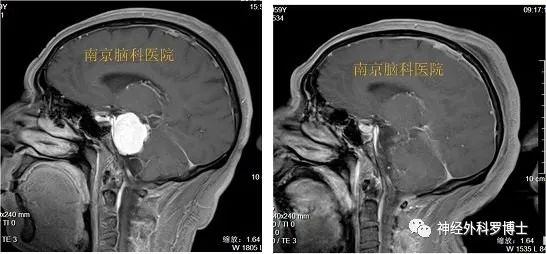

(见下图,左侧为术前,右侧为术后)

术前磁共振MRI增强显示岩斜区病变,后颅窝病变累及面神经水平,我们沿用改良扩大乙状窦后入路,在显微镜下行乙状窦后经天幕入路,术后1天磁共振复查显示肿瘤全切,术后患者恢复良好,没有不良症状发生。该入路方式相对于传统乙状窦后入路,既可以减少后颅窝神经的损伤,还可以更好的处理脑膜瘤基底,达到Simpson I级切除。